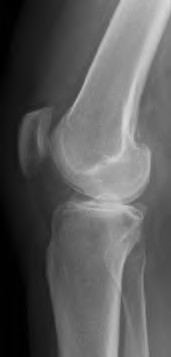

A 55-year-old male presents with isolated medial compartment osteoarthritis of the right knee. He is being evaluated for a medial unicompartmental knee arthroplasty (UKA). Which of the following physical examination or radiographic findings is an absolute contraindication to a medial UKA?

When planning a medial opening wedge high tibial osteotomy (HTO) for isolated medial compartment osteoarthritis in a varus knee, the surgeon intends to shift the mechanical axis to the Fujisawa point. Where is the Fujisawa point located on the tibial plateau?

Which of the following is traditionally considered an absolute contraindication to a medial mobile-bearing unicompartmental knee arthroplasty (UKA)?

When evaluating a patient for a Unicompartmental Knee Arthroplasty (UKA), which of the following is considered a classic absolute contraindication?

A 52-year-old male with isolated medial compartment osteoarthritis is evaluated for a unicompartmental knee arthroplasty (UKA).